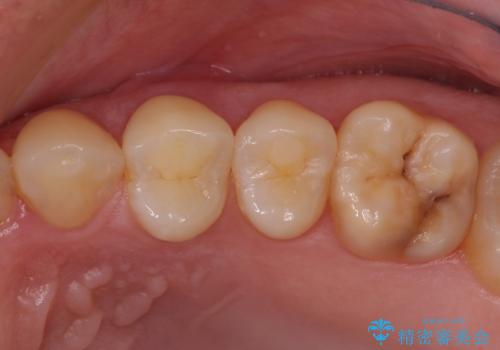

【根管治療】噛んだ時にしみる。最近になってズキズキ痛み、長引く痛みがある

担当医 河口智英